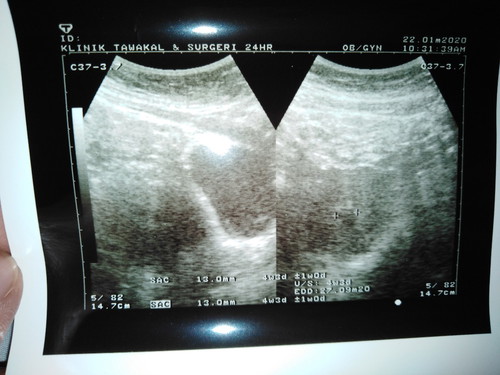

Hi mommies.. Mlm tdi ada Spotting mase buang air kecil.. Smpi ke pagi setiap kali buang air kecil akkn ada keluar bekuan drh kecil2.. Kdg2 mcm lendir drh.. Tapi langsung x de rasa sakit.. Bru g scan tdi dr ckp sac yg nmpk kecil sngt.. Dlm gmbr tue 4w3d tue mksdnyer 4 weeks ke..? Klu ikut kiraan apps nie last period first dah 23hb 11 so should be 8 weeks skrg.. Dr ckp mgkin x jadi.. ??? Mgkin salah kiraan.. Dr bagi ubat duphaston utk kuatkan janin.. Lagi 2 minggu dr suh dtg scan lagi.. Sape2 pnh experience mcm saya x.. Jadi mcm mane ye.. ?